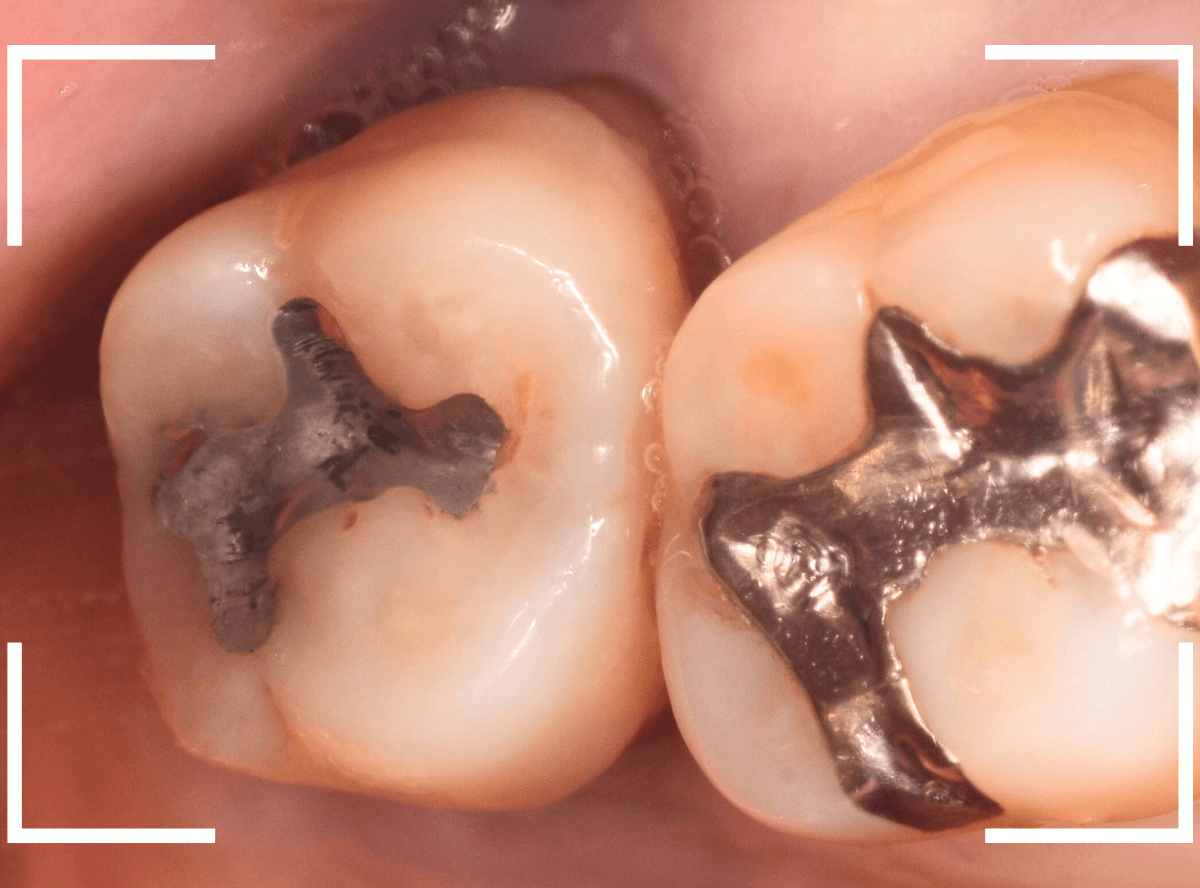

「一番奥の歯が揺れて痛む」という訴えで来院された患者さんのケースです。

歯肉に腫れなどはみられませんが、ピンセットで歯を揺らすとかなりグラグラしています。

歯肉の溝(歯周ポケット)も、かなり深くなっています。